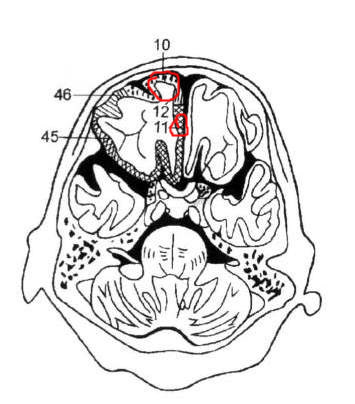

以下是引用hhcckk在2009-8-1 17:29:00的发言:[br]左侧额颞部囊状低密度影,边缘平直,有明显占位效应,考虑蛛网膜囊肿,病变导致左额颞部受压,精神症状可与此有关,李松年编的ct诊断学上有过介绍,额叶联合区损害可引起智力、性格、精神症状,也就是9、10、11区[br][br]